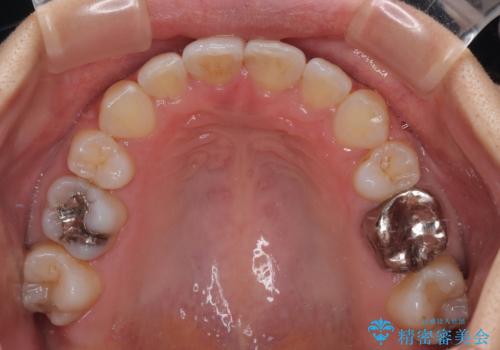

上下左右の第一小臼歯4本を抜歯して治療を行うことがセオリーでしたが、左下は第二小臼歯が銀歯であったため、イレギュラーではありますが、そちらを抜歯しました。

その影響で治療期間は長くなりましたが、処置していない歯を保存することができました。